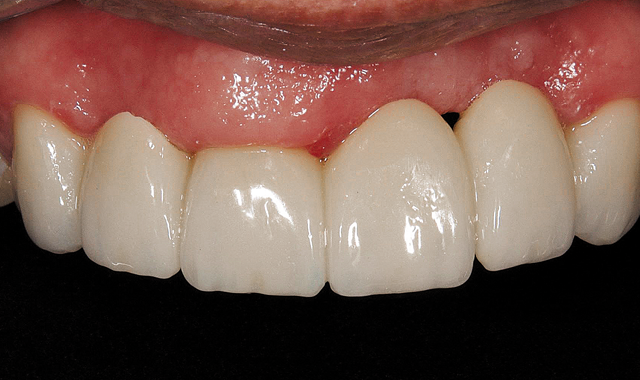

Fig. 6 Maxilar bucal view from final bridge from Connect Case

01 The doctor was presented with a patient who had a multitude of oral issues, including a collapsed bite, an underbite and several rotting teeth. The goal was to create an esthetically pleasing six-unit anterior bridge that would drastically change the patient’s appearance and lifestyle (Fig. 1).

03 The doctor then added some crownwork to the posterior region to raise the bite. As you can see from the image, this instantly made a major improvement to the overall appearance of the mouth. With this particular alteration, the patient was now on his/her way to having a normal, functional bite and a more esthetically pleasing smile (Fig. 3).